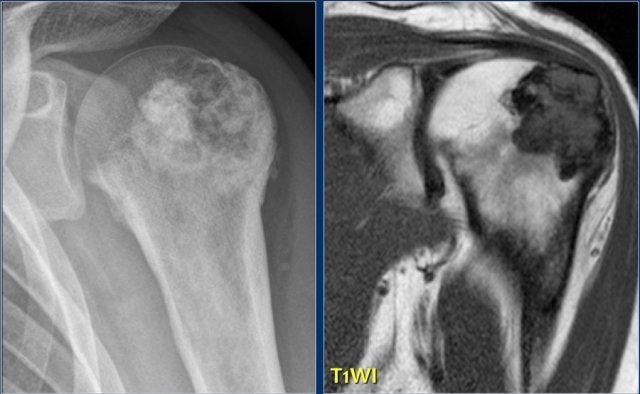

Đây là tổn thương nằm ở vùng đầu xương và hành xương của đầu trên xương cánh tay.

Tổn thương chủ yếu bị vôi hóa.

Hình ảnh T1W mặt phẳng vành tai cho thấy bờ tổn thương có dạng thùy và tín hiệu thấp ở ngoại vi do các vôi hóa.